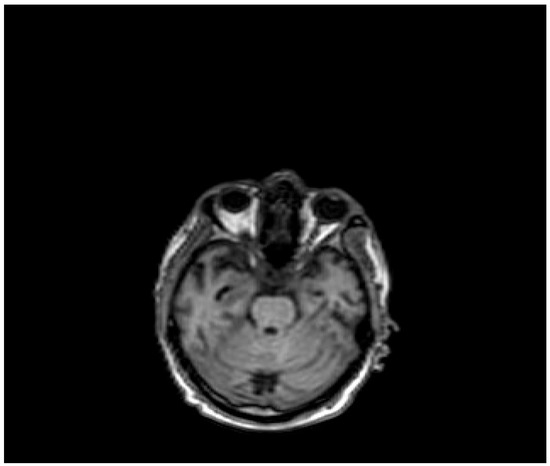

| Pt 7, M, 71, 2025 | HHD, cognitive involutional syndrome | High fever, headache, confusion, worsening motor difficulty with lower limb weakness | +/+ | Neg | Neg | Neg | ICH of the occipital horns of the lateral ventricles (Figure 2) | Diffuse meningoencephalitis, with involvement of the cauda extremity roots. ICH of the occipitopolar and bihemispheric mid-posterior cingulate sulci, the left temporoparietal carrefour, and the fourth ventricle, occipital horns, and pericerebellar cistern. Posterior dorso-lumbo-sacral, anterior dorso-lumbar (up to L1), and sacral epidural hematoma (Figure 3 and Figure 4) | DEX, Igs | Gradual clinical improvement, however lower limb weakness persisted | Transferred to a rehabilitation facility 34 days after hospital admission. | |

Figure 2.

Evidence of an extensive epidural spinal cord hematoma on spinal MRI (Table 1, patient 7).

Figure 4.

Evidence of ICH on brain MRI (Table 1, patient 7).